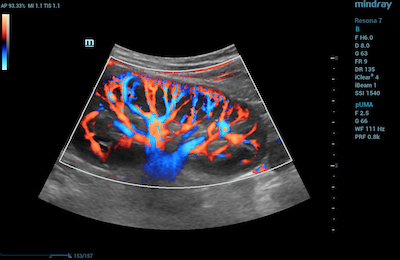

- Directional Power Doppler Ultrasound– This form of imaging encompasses the flow information provided by CDI with the anatomic acuity associated with Power Doppler ultrasound.

Directional Power Doppler ultrasound of Common Renal Perfusion

Directional Power Doppler ultrasound of Carotid Artery and Carotid Bifurcation